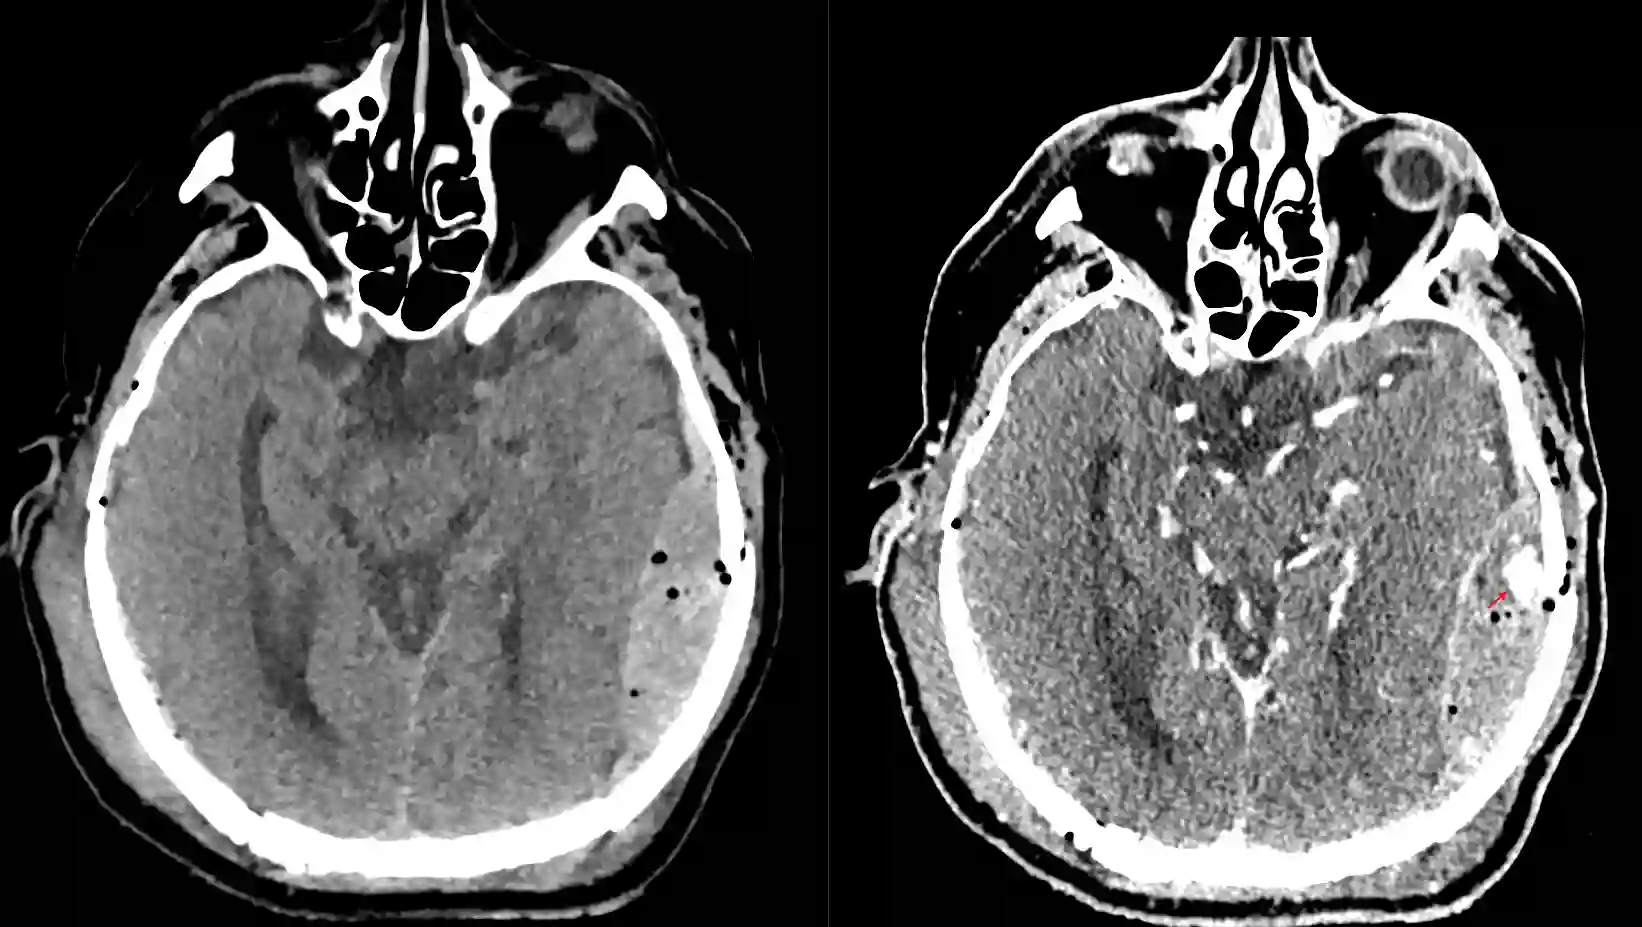

Spot Sign im Ct

Darstellung des Spot Signs (roter Pfeil) in einem CT bei einem Patient mit einem linksseitigen Epiduralhämatom. Linksseitig natives CT Bild und rechtsseitig ein CT nach Kontrastmittelgabe.